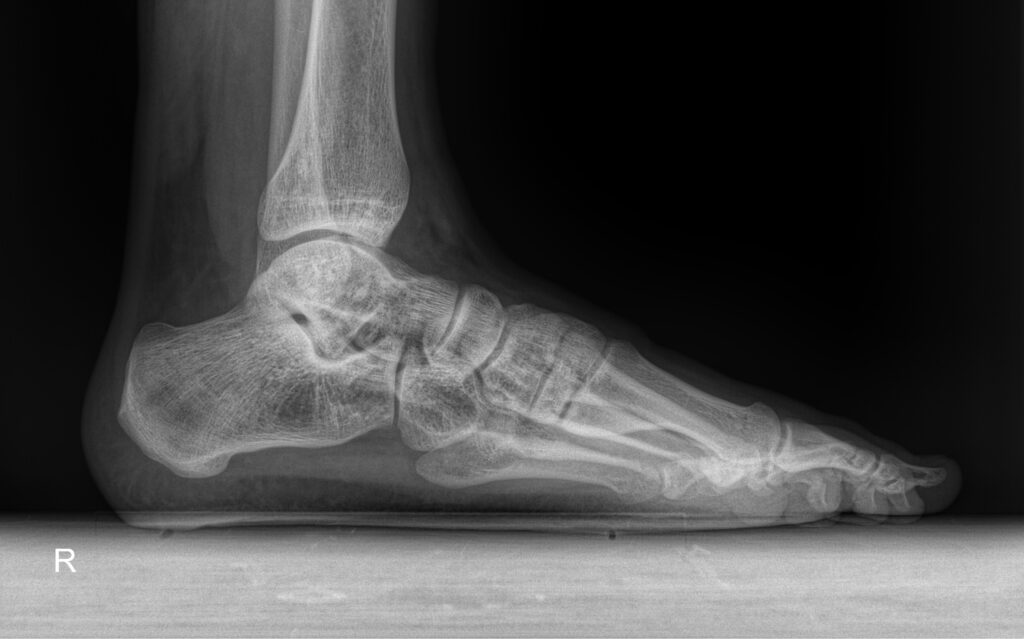

-голеностопный сустав (вывих, перелом, артрит, плоскостопие и др.);